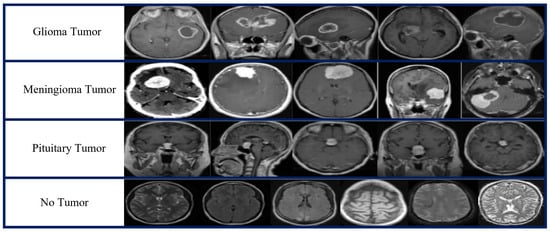

| Tumor Type | No of MRI Images | MRI Views |

|---|---|---|

| Glioma tumor | 926 | Axial, coronal, sagittal |

| Meningioma tumor | 937 | Axial, coronal, sagittal |

| Pituitary tumor | 901 | Axial, coronal, sagittal |

| No tumor | 501 | |

| Total number of images | 3265 |